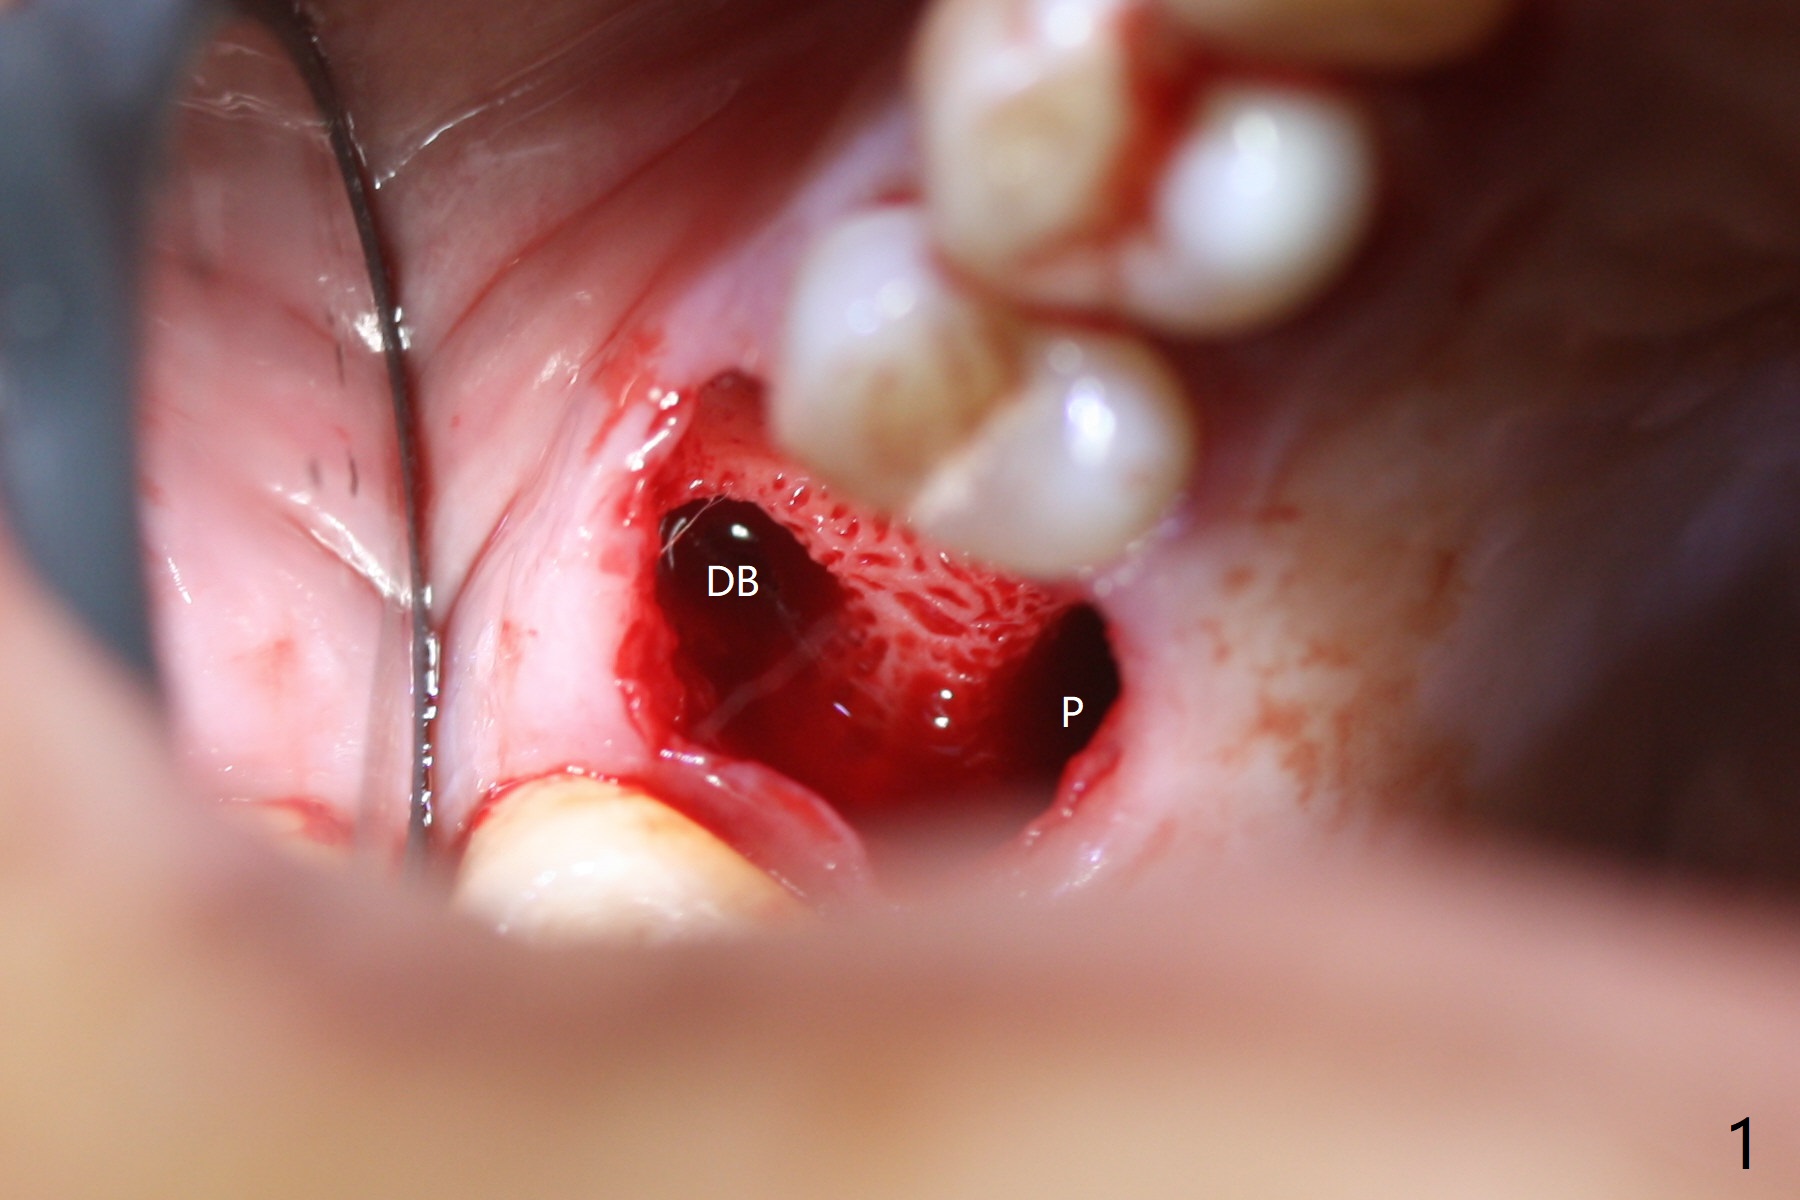

While the tooth #3 has a mesiodistal crack line, etiology may be due to chronic periodontitis with bruxism. After extraction, there is granulation tissue attached to the distobuccal (DB) root. The DB socket is larger than the mesiobuccal one (Fig.1). Osteotomy is initiated in the DB slope of the septum for 10 mm (Fig.2,3). Since there is ample apical bone, the depth of the osteotomy increases to 11.5 mm. When a 5x10 mm dummy implant is placed, primary stability is satisfactory (Fig.4 (yellow line: apical space)). The definitive implant remains the same dimension with deeper placement (Fig.5,6 (~ 20 Ncm)); with placement of a 6.5x4(3) mm abutment and Vanilla/Osteogen Graft (*), an immediate provisional is fabricated in place (without taking out for trimming) with sufficient clearance with the opposing dentition. It appears that the moderately long implant (10 mm) is able to achieve primary stability for immediate placement. When the provisional is removed 2 months postop, bone graft seems to be adhered to the socket (Fig.7). To improve local hygiene, the provisional does not return. The implant seems to have osteointegrated 3.5 months postop (Fig.8). The crown/abutment is loose approximately 1 year post cementation. Due to her daughter's contracting COVID 19, she postpones returning for approximately 1 year. The access hole is opened, crown/abutment (6.5x4(4) mm) removed, proximal contacts reduced, crown/abutment reseated without certainty. BW shows incomplete seating probably due to bony interference (Fig.9). A 5.5x4(4) mm can not be seated (bouncing, probably due to soft tissue interference). When a 4.5x5(4) mm abutment (UF) is seated, hand tightening is smooth, confirmed by BW (Fig.10). Two weeks later, the new crown is cemented intraorally. The crown/abutment is removed for cleaning. The abutment screw is torqued at 20 NCM.